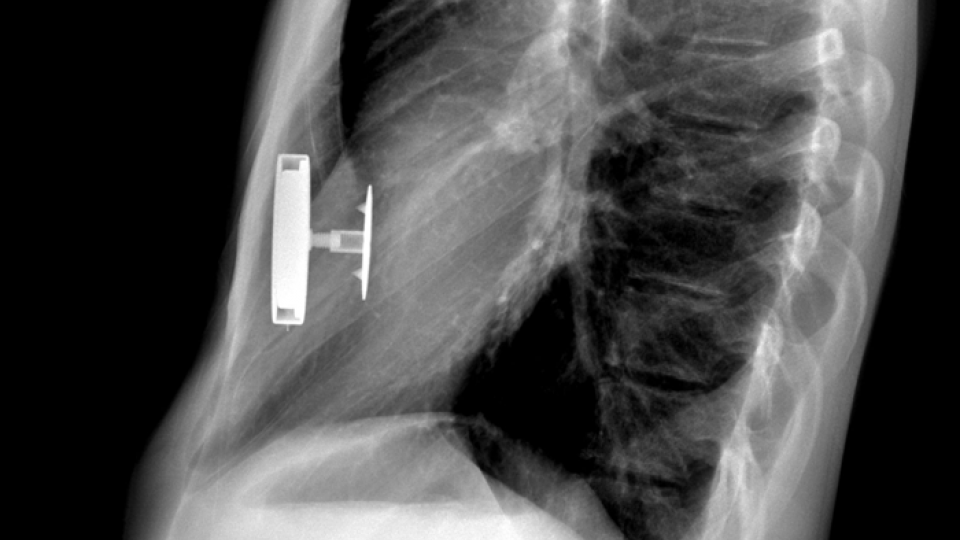

From www.sciencephoto.com

Sunken chest, 3D CT scan Stock Image C026/8360 Science Photo Library How Rare Is A Sunken In Chest Pectus excavatum, also known as “sunken chest” or “funnel chest,” is a congenital condition where the breastbone (sternum) and rib cartilage develop abnormally, causing the middle of the chest. Your doctor may suggest several different types of tests to check for associated problems with the heart and. Men experience sunken chest at a much higher rate than women. Pectus excavatum. How Rare Is A Sunken In Chest.